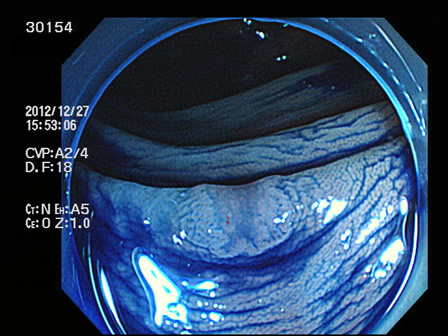

上記100名より抽出した平坦・陥凹型腺腫(=癌化の危険が高いが見落としやすい病変)の内視鏡写真